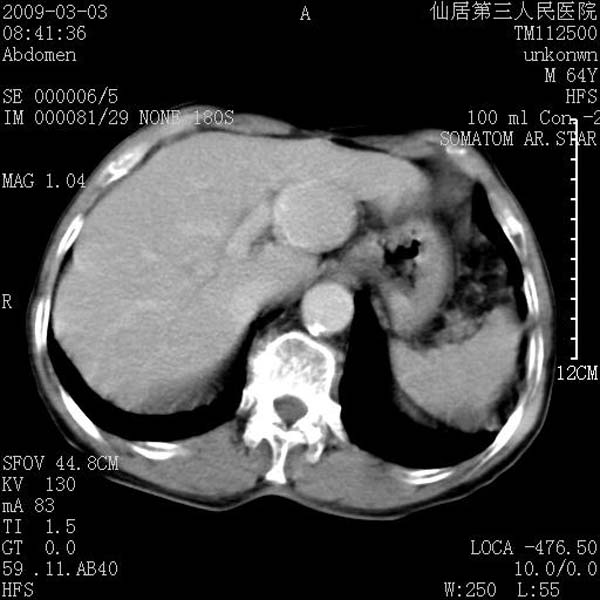

标题: CT18469:男性,64y,体检B超示肝脏低回声肿块,有胃溃疡手术 [打印本页]

患者,男性,64y,体检b超示肝脏低回声肿块,有胃溃疡手术史。

考虑----胃肠道间质瘤可能性大

从平扫及增强的特点来看,支持肝脏腺瘤并出血。

考虑胃间质瘤可能性大。

胃肠道间质瘤!

ct值呢?感觉没强化,象囊性。

考虑肝静脉韧带裂区良性占位性病变(囊肿?)。

考虑肝囊肿并出血可能性大.

考虑高密度囊肿可能性大